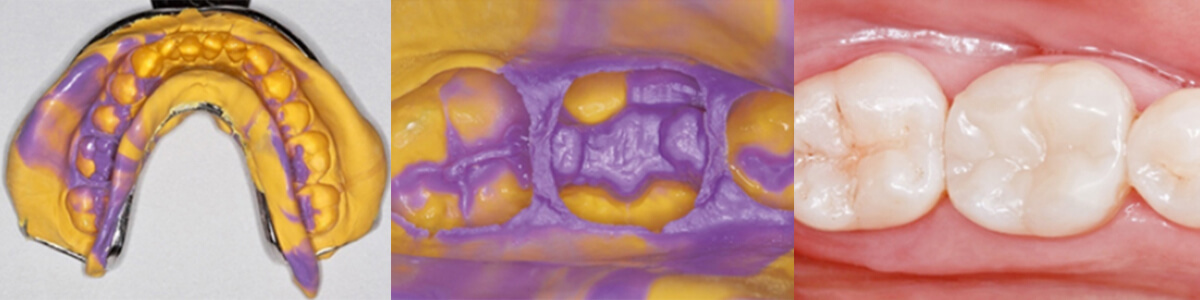

Dans la pratique clinique quotidienne, l'enregistrement de l'occlusion joue un rôle essentiel dans de nombreuses spécialités dentaires : de la réhabilitation prothétique à l'orthod

La prise d'une empreinte dentaire précise est une étape essentielle pour garantir le succès de toute restauration.

La prise d'empreintes dentaires est une procédure essentielle en dentisterie, car elle fournit un enregistrement précis de l'anatomie buccale du patient pour la fabrication de prot